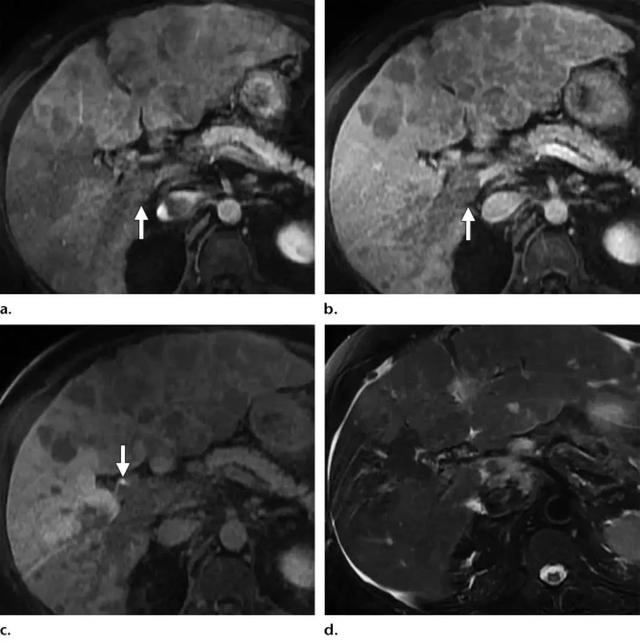

格艾选读丨肝脏影像检查技术ctmri

肝脏典型良性肿瘤mri表现

肝脏病变的mr诊断

肝脏常见肿瘤mri诊断与鉴别诊断

肝细胞肝癌磁共振表现有哪些

肝脏肿瘤mri诊断